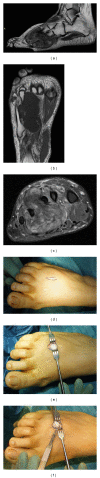

In the management of bone and soft tissue tumors, accurate diagnosis, using a combination of clinical, radiographic, and histological data, is critical to optimize outcome. On occasion, diagnosis can be made by careful history, physical examination, and images alone. However, the ultimate diagnosis usually depends on histologic analysis by an experienced pathologist. Biopsy is a very important and complex surgery in the staging process. It must be done carefully, so as not to adversely affect the outcome. Technical considerations include proper location and orientation of the biopsy incision and meticulous hemostasis. It is necessary to obtain tissue for a histological diagnosis without spreading the tumor and so compromise the treatment. Furthermore, the surgeon does not open compartmental barriers, anatomic planes, joint space, and tissue area around neurovascular bundles. Nevertheless, avoid producing a hematoma. Biopsy should be carefully planned according to the site and definitive surgery and should be performed by an orthopedic surgeon with an experience in musculoskeletal oncology who will perform the definitive surgery. Improperly done, it can complicate patient care and sometimes even eliminate treatment options. Different biopsy techniques are suitable: fine-needle aspiration, core-needle biopsy, and incisional biopsy. The choice of biopsy depends on the size, the location of the lesion, and the experience of the pathologist.